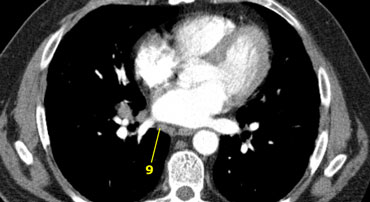

9. Pulmonary Ligament

Nodes lying within the pulmonary ligaments.